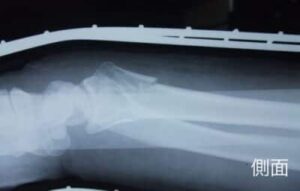

【橈骨遠位端骨折】コーレス骨折の治療とリハビリ|手術以外の選択肢と後遺症…